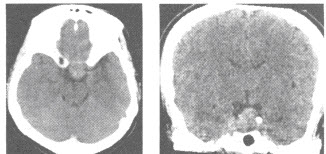

女,42岁,泌乳2个月,平扫CT检查如图,最可能的诊断为()

A:颅咽管瘤

B:垂体瘤

C:脊索瘤

D:脑膜瘤

E:正常